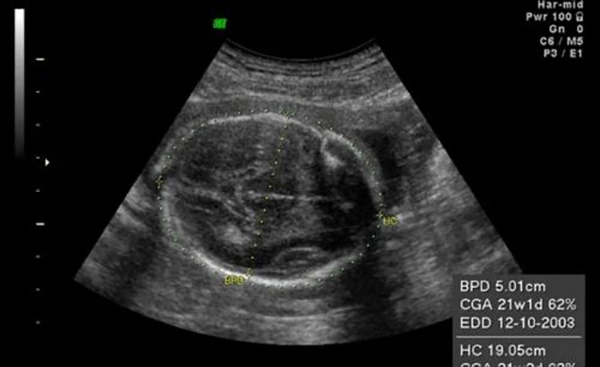

Đường kính lưỡng đỉnh (thông số BPD) là kích thước đo được tại mặt cắt lớn nhất của vùng từ trán ra sau gáy của thai nhi. Một cách đơn giản, đây chính là đường kính phần đầu thai nhi. Phương pháp siêu âm được áp dụng để xác định đường kính lưỡng đỉnh thai.

Khi thai bước vào tuần thứ 13 trở đi, mẹ bầu có thể siêu âm để biết các chỉ số đường kính lưỡng đỉnh, chi vi đầu, chiều dài xương,…của thai nhi. Trong suốt thai kỳ, đường kính lưỡng đỉnh thai thay đổi rất nhanh. Đường kính lưỡng đỉnh thai 37 tuần là một chỉ số quan trọng biểu hiện tình trạng thai nhi ở giai đoạn chuẩn bị chào đời.

Đường kính lưỡng đỉnh thai 37 tuần 1 ngày bình thường khoảng 86-94 mm. Đường kính trung bình 90 mm là tốt nhất, cho thấy thai nhi phát triển ổn định. Các chỉ số khác ở thời điểm này như sau:

Đường kính lưỡng đỉnh của thai nhi ở tuần 13 đến tuần 40 của thai kỳ luôn trong mức từ 88-100 mm. Tại tuần 37 của thai kỳ, đường kính lưỡng đỉnh không vượt quá 94 mm. Nếu qua siêu âm kiểm tra cho thấy đường kính lưỡng đỉnh quá lớn thì có nguy cơ gây trở ngại cho mẹ bầu khi sinh. Ngược lại nếu đường kính lưỡng đỉnh quá nhỏ tức là thai chậm phát triển hơn bình thường.